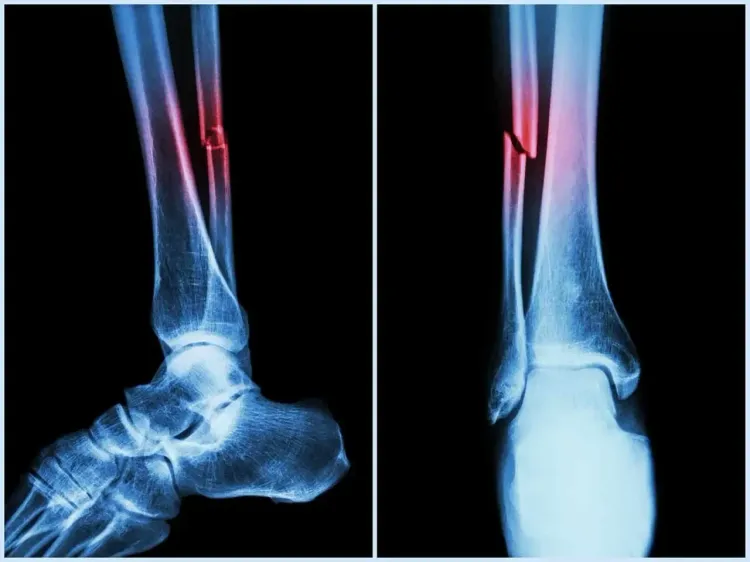

नई दिल्ली, 13 अगस्त (राष्ट्र प्रेस)। राष्ट्रीय प्रौद्योगिकी संस्थान (एनआईटी) राउरकेला के शोधकर्ताओं ने यह खोजा है कि मानव शरीर में पाए जाने वाले प्राकृतिक शर्करा जैसे अणु हड्डियों के निर्माण और मरम्मत में सहायक प्रोटीन के कार्यों में बदलाव ला सकते हैं।

यह अध्ययन बायोकेमिस्ट्री पत्रिका में प्रकाशित हुआ है। इसके परिणामों का उपयोग हड्डियों और कार्टिलेज के पुनर्जनन के उन्नत उपचार, बेहतर प्रत्यारोपण और प्रभावी प्रोटीन-आधारित दवाओं के विकास में किया जा सकता है।

इस संदर्भ में एनआईटी की टीम ने कहा कि बोन मॉर्फोजेनेटिक प्रोटीन-2 (बीएमपी-2) हड्डियों और कार्टिलेज के निर्माण, चोटों के उपचार और स्टेम कोशिकाओं को अस्थि-निर्माण कोशिकाओं में परिवर्तित करने में महत्वपूर्ण भूमिका निभाता है।

यह शोध अस्थि भंग, रीढ़ की हड्डी की चोटों और अपक्षयी अस्थि रोगों के उपचार के लिए बेहतर जैव पदार्थ और दवा वितरण प्रणाली विकसित करने में मदद कर सकता है। यह उपचार के दौरान दवा वितरण को अनुकूलित करने और रोगियों के लिए दुष्प्रभावों को कम करने में भी सहायक हो सकता है।